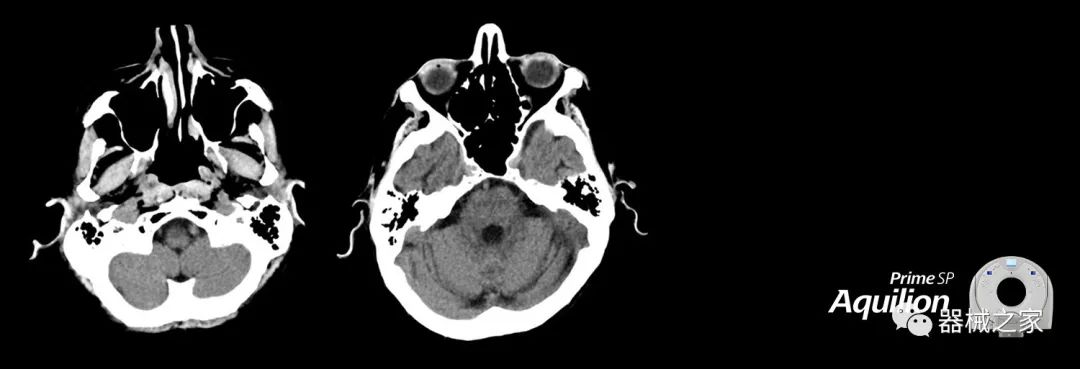

在以患者為中心的放射腫瘤學(xué)領(lǐng)域,計(jì)算機(jī)斷層掃描(CT)的可訪問性,可重復(fù)性和靈活性至關(guān)重要。為了建立這些價(jià)值,佳能醫(yī)療系統(tǒng)美國公司現(xiàn)在正在擴(kuò)大其放射腫瘤學(xué)CT模擬產(chǎn)品,包括Aquilion Prime SP和Aquilion Lightning 80高級(jí)CT系統(tǒng)。除了Aquilion LB之外,Aquilion Prime SP和Aquilion Lightning 80現(xiàn)在還包括放射治療(RT)選項(xiàng),可為腫瘤學(xué)規(guī)劃提供高質(zhì)量的CT成像和精密工具。

擴(kuò)展視野(EFOV)可以看到更多的解剖結(jié)構(gòu)。Aquilion LB采用85 cm EFOV,而Aquilion Prime SP和Aquilion Lightning 70采用70 cm EFOV。

Aquilion Prime SP使設(shè)施能夠處理具有挑戰(zhàn)性的案例,同時(shí)為員工提供快速,靈活和高效的解決方案。

兩個(gè)CT系統(tǒng)均采用0.5 mm x 80排PUREViSION探測(cè)器技術(shù)(可配置并從80-160現(xiàn)場(chǎng)升級(jí)),78 cm孔徑,50 cm視野,AIDR(自適應(yīng)迭代劑量減少)3-D和SEMAR(單個(gè))能量金屬神器減少)技術(shù)。

Aquilion LB專為滿足腫瘤學(xué)挑戰(zhàn)而設(shè)計(jì),同時(shí)優(yōu)先考慮患者護(hù)理。Aquilion LB的內(nèi)徑為90 cm,能夠幫助復(fù)雜的患者設(shè)置并提高患者的舒適度。CT模擬定位可以輕松鏡像放射治療定位,更加自信。該系統(tǒng)采用0.5 mm x 16排(32層)PUREViSION探測(cè)器技術(shù),70 cm視野,AIDR 3D和SEMAR技術(shù)。